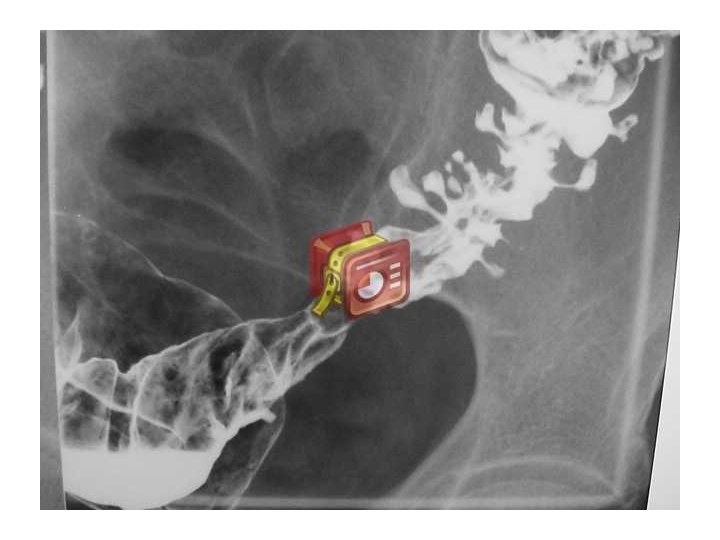

ENFERMEDAD DIVERTICULAR DE COLON • Divertículo: • Protrusión sacular de la mucosa a través de la pared muscular del colon • La protrusión ocurre en las áreas débiles de la pared intestinal donde pueden penetrar los vasos sanguíneos • Habitualmente 5– 10 mm de tamaño • Los divertículos son realmente pseudodivertículos (falsos divertículos), ya que contienen sólo mucosa y submucosa cubiertas de serosa

Enfermedad diverticular • Diverticulosis – presencia de divertículos dentro del colon • Diverticulitis – inflamación de un divertículo • Sangrado diverticular Tipos de enfermedad diverticular • Simple: 75% no tienen complicacionesli> • Complicada: 25% presentan abscesos, fístulas, obstrucción, peritonitis, sepsis

• Distribución – Compromiso sigmoideo – Sólo sigmoideo – Todo el colon – Próximo al sigmoides 95% 65% 7% 4% • Historia Natural – Asintomática – Evoluciona a diverticulitis – Se asocia a sangrado 70% 15– 25% 5– 15%

Divertículos de colon